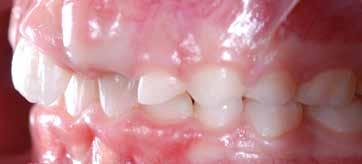

Presentazione del caso > F.V, bambino di cinque anni, presenta una malocclusione di II Classe scheletrica, III Classe dentale molare e canina destra e sinistra, morso inverso anteriore. Le arcate dentali mostrano usura degli elementi dentari anteriori a causa dell’occlusione patologica. Le linee mediane, superiore ed inferiore, sono centrate; il frenulo labiale superiore patologico per un’eccessiva estensione inter-incisale.

Il piano di trattamento prevede l’utilizzo di un dispositivo elastodontico di III Classe, da portare per due ore diurne e tutte le notti in modo passivo, senza effettuare alcun esercizio, al fine di ripristinare una relazione molare e canina bilaterale di I Classe ed il corretto avanzamento maxillare e inibire l’eccessiva crescita mandibolare. È possibile ottenere il risultato in pochissimi mesi di terapia, essendo la crescita del paziente molto attiva.

In un secondo momento, alla risoluzione della problematica scheletrica, si monitorizzerà il caso con visite semestrali in modo da reintervenire qualora si dovesse ripresentare la problematica.

Dall’esame clinico si evince la III Classe dentale, l’inversione anteriore e l’over-jet negativo.